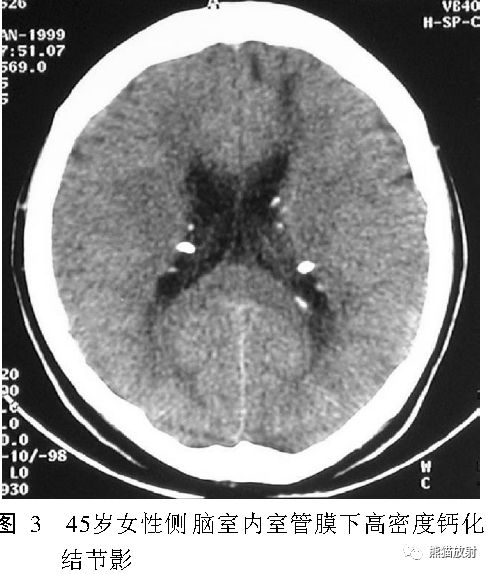

颅内结节性硬化可出现典型的 4种类型的病理改变: 皮质结节、脑白质异常、室管膜下结节、室管膜下巨细胞星形细胞瘤。

- 室管膜下钙化小结节(<1.3cm) ; 室管膜下巨细胞性星形细胞瘤 (>1.3cm) ,绝大多数位于室间孔

- 室管膜下结节;